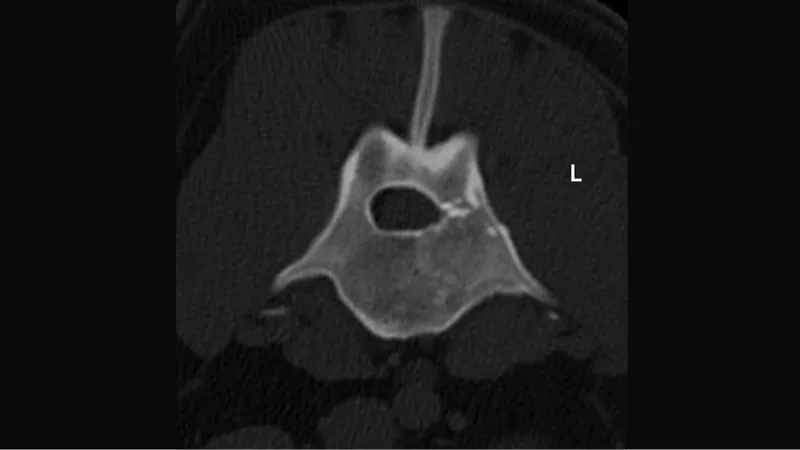

Figure 1: CT scan of the lumbar spine, showing a comminuted vertebral body and pedicle fracture of L3. Fracture fragments are visible within the spinal canal, compressing the spinal cord.

A one-year-old neutered male Cane Corso was brought to the small animal hospital after being hit by a car. He was lethargic and unable to walk. He presented with monoplegia with deep pain in the right hind limb and monopareses in the left hind limb. The tail was uniformly paralyzed. The neurological localization for the suspected vertebral damage was identified as the mid- to caudal-lumbar region. After initial stabilization, a CT scan was performed and revealed a highly comminuted compression fracture of the L3 vertebral body and pedicle on the left side. Multiple fracture fragments were visible within the spinal canal compressing the spinal cord (Figure 1).